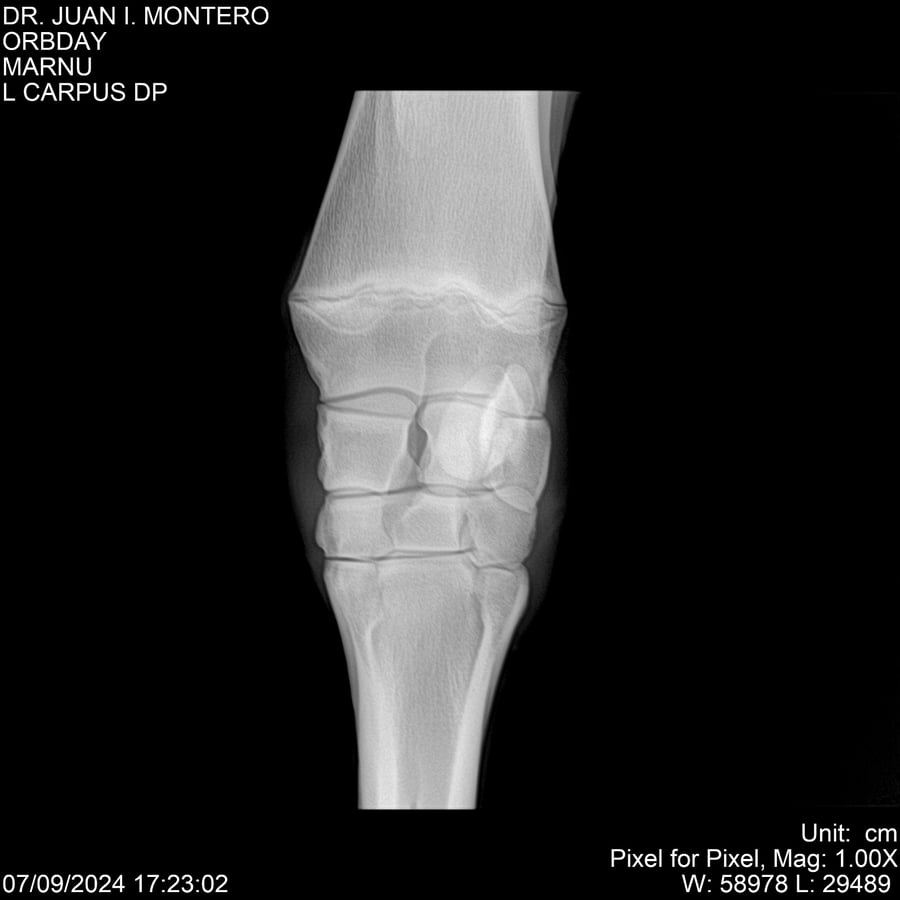

• Empresa: Abelenda N. R., Walter Hugo